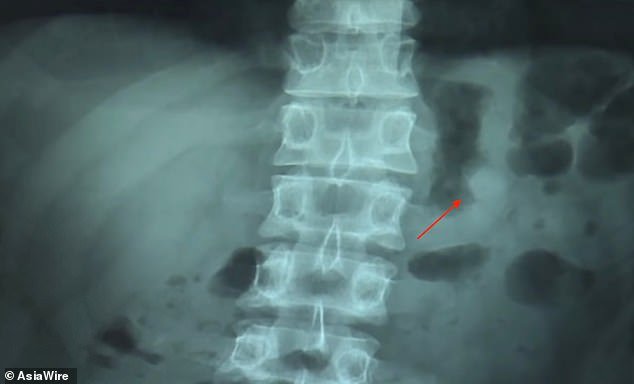

O sadəcə olaraq bildirib ki, hər iki qulaqlıq qulaqlarına taxılı vəziyyətdə yuxuya gedib və səhər oyananda görüb ki, sadəcə olaraq bir qulaqlıq var. Find My AirPods funksiyası vasitəsilə Ben qulaqlığa siqnal göndərib və aşkar edib ki, qulaqlığın bir tayı onun mədəsində yerləşir. Heç bir diskomfort yaşamasa da Ben dərhal xəstəxanaya yollanıb. Xəstəxanada edilmiş rentgen öz növbəsində təsdiq edib ki, AirPods-un bir tayı həqiqətən də Ben-in mədəsində yerləşir.